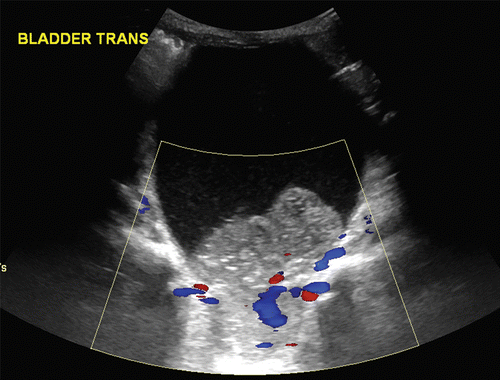

What is the most common bladder malignancy in kids

A

Rhabdomyosarcoma

• 20% mets

• 20% ocurre in the bladder or prostate region

• Most of the rhabdos are actually in the orbit or nasopharynx.

• Bimodal 2-4 and 15-17

• Li Fraumeni cancer and NF1

• Paratesticular tumors are the only genitourinary tract rhabdomyosarcomas that tend to occur in older children, typically adolescents.